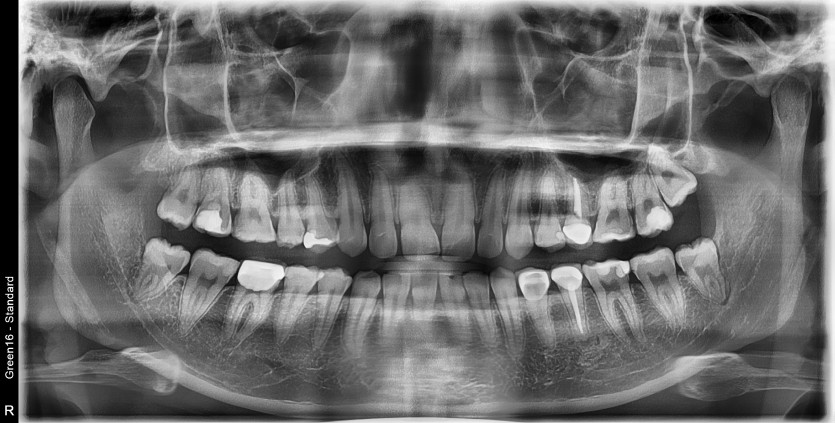

#18,48 사랑니 발치

구강 외과 전문의가 당일 발치했습니다.